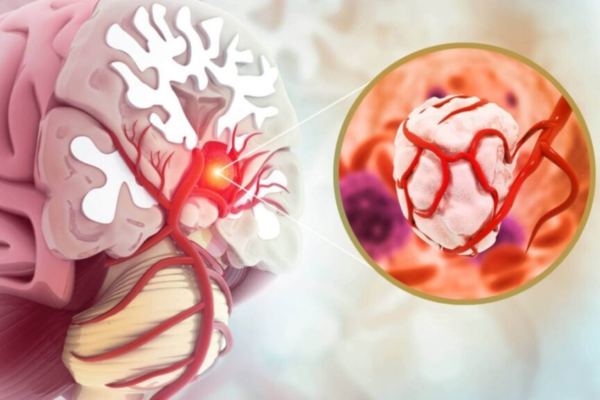

Aneurysm coiling is a minimally invasive procedure used to treat brain aneurysms by preventing rupture. It is performed when weakened blood vessels balloon and pose a serious risk of bleeding.

Cranial vascular malformations cause abnormal connections between arteries and veins, leading to bleeding, seizures, or neurological deficits.

Embolization blocks these abnormal vessels using specialized materials, restoring normal blood flow and reducing the risk of life-threatening brain hemorrhage.